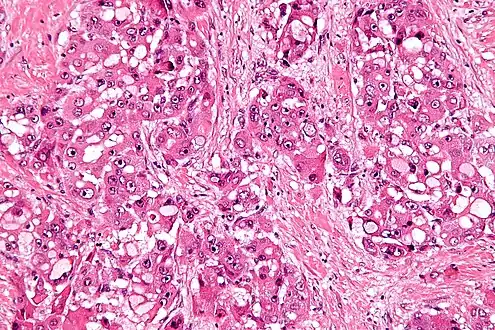

| Micrograph of fibrolamellar hepatocarcinoma showing the characteristic laminated fibrosis between the tumor cells with a low NC ratio. H&E stain. | |

The histopathology of FLC is characterized by laminated fibrous layers, interspersed between the tumor cells. Cytologically, the tumor cells have a low nuclear to cytoplasmic ratio with abundant eosinophilic cytoplasm.[1] Tumors are non-encapsulated, but well circumscribed, when compared to conventional HCC (which typically has an invasive border).